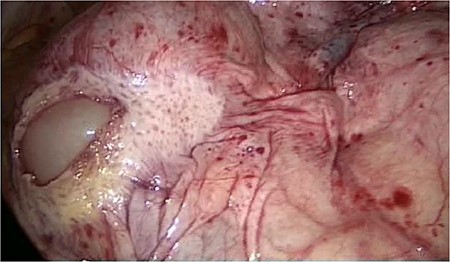

We accidentally opened the dorsal peritoneum (Fig. 2), and found the small bowel underneath - retroperitoneal (Fig. 3).

Even the terminal ileum seemed to be retroperitoneal. The slim preperitoneal appendix and the terminal retroperitoneal ileum are demonstrated in Fig. 4. The entire ileum was covered by the peritoneum.